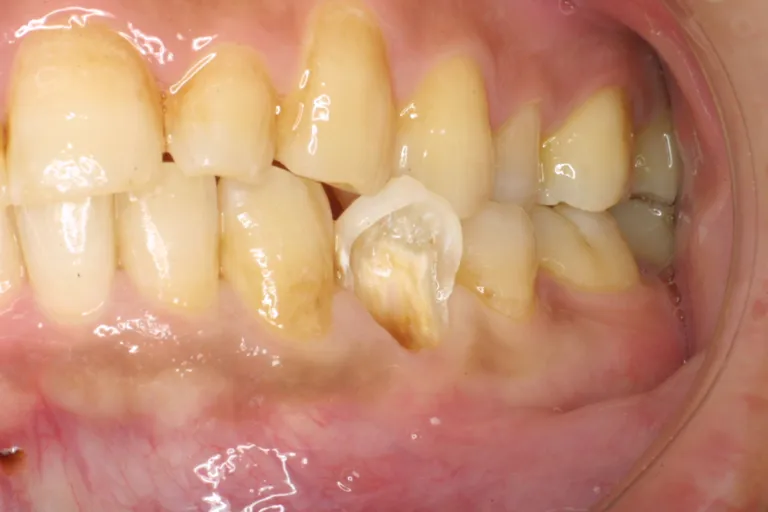

■術前・他医院で治療された被せもので精度が低く歯との境の縁があっていないため段差ができています

■術 前■

被せ物の縁が

あっていない

■術前・被せものはセメントを盛って取付け段差を埋めますが縁の制度が低いと境目のセメントが取れた時に大きな段差ができます